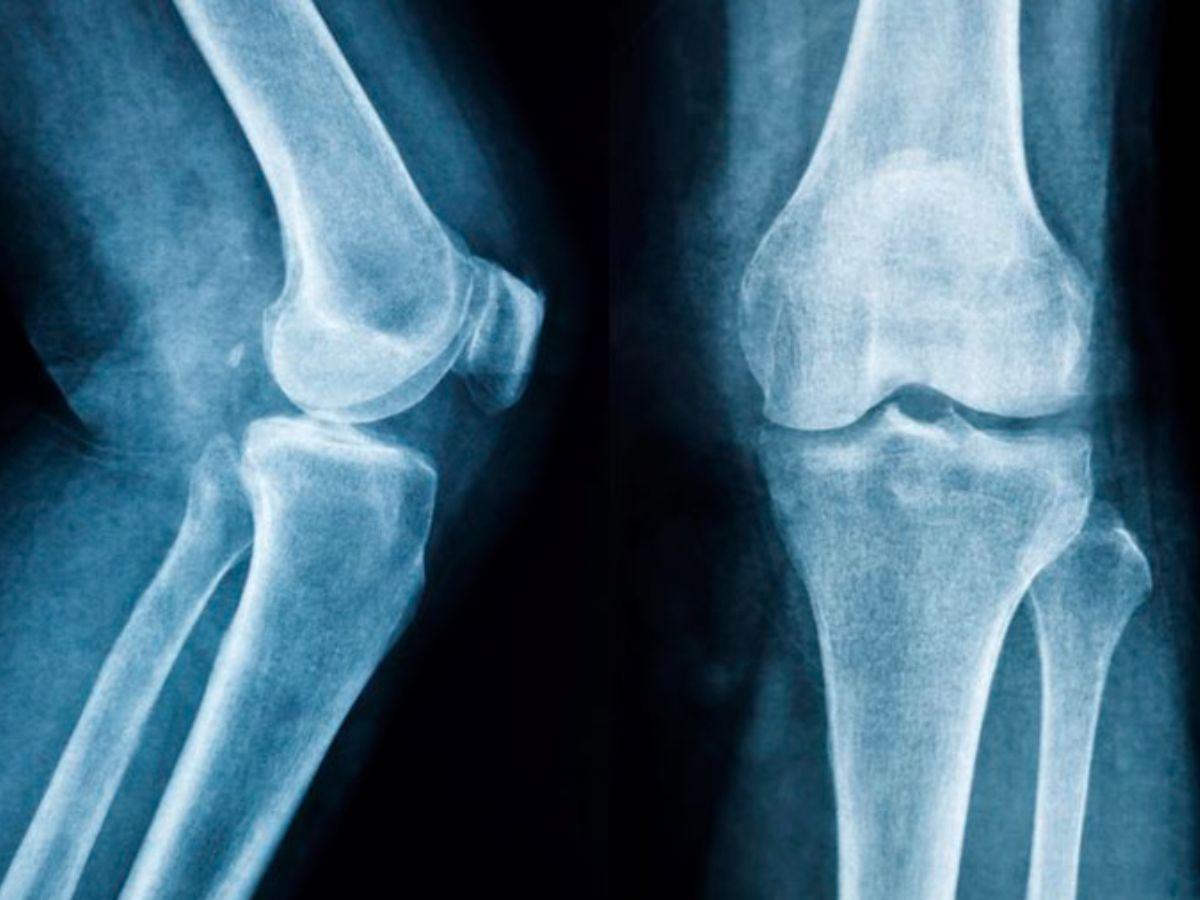

Cấu tạo khớp gối

Đầu gối là bộ phận kết nối hai phần xương ống chân và cẳng chân, kết cấu khớp có biên độ vận động lớn và có vai trò cực kỳ quan trọng trong quá trình di chuyển của cơ thể. Cấu tạo chính của khớp gối bao gồm:

Xương khớp gối: Bao gồm phần đầu dưới xương đùi, xương bánh chè và đầu trên xương chày. Trong số đó, phần xương bánh chè là bộ phận dễ bị tổn thương khi có tác động lực mạnh đến phần đầu gối, gây ảnh hưởng nghiêm trọng đến quá trình co duỗi và chuyển động của chân.